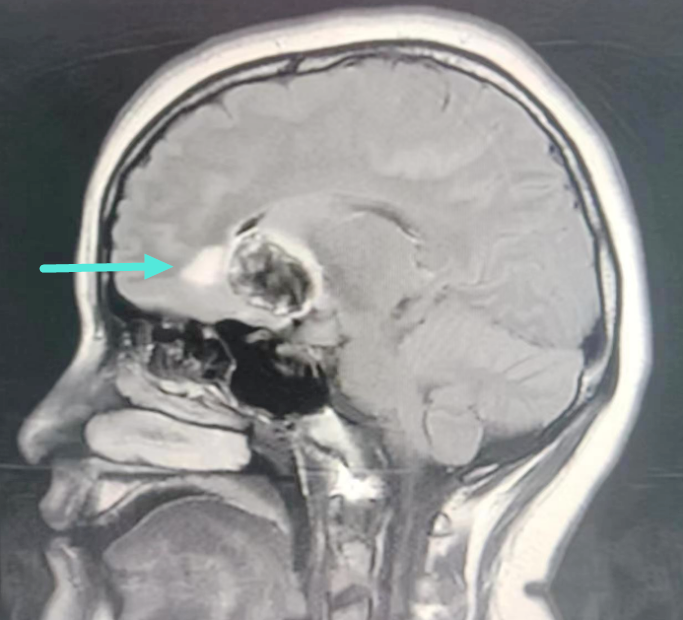

近日一女子因“反复头痛”症状到我院治疗,经详细检查后,发现右侧额叶深部血管瘤。神经外科学科带头人、副院长王鹏与神经外科二区负责人叶志其会诊后认为:患者诊断考虑为右侧额叶深部-基底节区海绵状血管畸形伴发育性静脉异常并出血,病灶体积大、结构复杂,已反复出血并导致头痛、呕吐等症状,如病情继续发展,将出现严重的颅高压症状,甚至有生命危险,神经外科团队迅速与患者家属沟通,为患者制定最佳治疗方案。

▲MRI提示右侧额叶深部-基底节区海绵状血管

畸形伴发育性静脉异常并出血